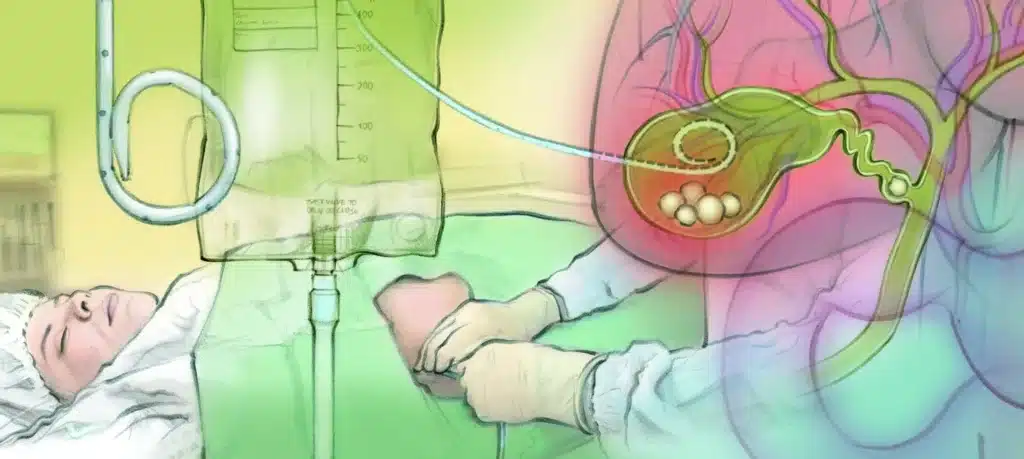

Η διαδερμική χολοκυστοστομία είναι σήμερα η πιο διαδεδομένη και «κλασική» μορφή χολοκυστοστομίας:

- Εκτελείται από επεμβατικό ακτινολόγο ή χειρουργό.

- Χρησιμοποιείται τοπική αναισθησία και ήπια μέθη, όχι γενική αναισθησία.

- Περνά οδηγός σύρμα και πάνω σε αυτό τοποθετείται λεπτός καθετήρας (pigtail) που καθηλώνεται στο δέρμα και συνδέεται με σακουλάκι συλλογής.

- Οξεία χολοκυστίτιδα σε ασθενή υψηλού ή απαγορευτικού χειρουργικού κινδύνου.

- Σηπτικοί ασθενείς, ασθενείς σε ΜΕΘ, σε σοβαρή καρδιοαναπνευστική ανεπάρκεια.

- + Δεν χρειάζεται γενική αναισθησία.

- + Ελάχιστα επεμβατική, μικρός τραυματισμός, γίνεται ακόμη και σε πολύ βαρείς ασθενείς.